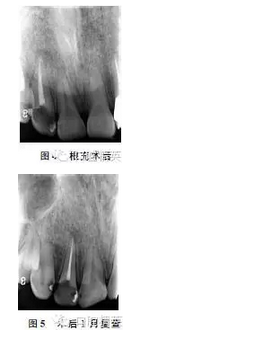

慢性根尖周炎在臨床上往往表現(xiàn)為牙齦瘺管,該瘺管常開口于病灶牙根尖部位的頰側(cè)牙齦,管口大多呈突起于黏膜的粟粒狀肉芽,其形態(tài)、位置可發(fā)生變異。這種有瘺型慢性根尖周炎患牙往往無明顯牙疼癥狀,那么瘺管來源的確定對于患牙確診就顯得尤為重要。

對于大多數(shù)伴有瘺管的的慢性根尖周炎患牙,即便瘺管開口于病源牙遠(yuǎn)處,牙膠尖示蹤法都能找到病源牙,然而對于形態(tài)變異的瘺管,牙膠尖通過瘺道往往不能指示到病源牙。

此時臨床上大多采取診斷性治療進(jìn)行患牙的確診,但是當(dāng)有多個可疑牙時,診斷性治療不免會給患者帶來一些不必要的痛苦,隨著錐形束CTCBCT)在口腔醫(yī)學(xué)領(lǐng)域的廣泛應(yīng)用,CBCT開始運(yùn)用于慢性根尖周炎根尖組織破壞的診斷,而且取得了較好的臨床效果。本例病例就是運(yùn)用CBCT技術(shù)檢查病源牙及多個可疑牙的根尖組織情況,從而發(fā)現(xiàn)瘺管來源,進(jìn)而確診病源牙。